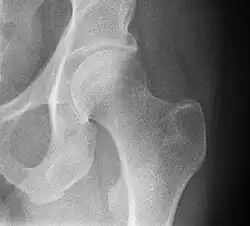

![]() Bones of the hip region | |

In vertebrate anatomy, the hip, or coxa[1] (pl.: coxae) in medical terminology, refers to either an anatomical region or a joint on the outer (lateral) side of the pelvis.

The hip region is located lateral and anterior to the gluteal region, inferior to the iliac crest, and lateral to the obturator foramen, with muscle tendons and soft tissues overlying the greater trochanter of the femur.[2] In adults, the three pelvic bones (ilium, ischium and pubis) have fused into one hip bone, which forms the superomedial/deep wall of the hip region.

The hip joint, scientifically referred to as the acetabulofemoral joint (art. coxae), is the ball-and-socket joint between the pelvic acetabulum and the femoral head. Its primary function is to support the weight of the torso in both static (e.g. standing) and dynamic (e.g. walking or running) postures. The hip joints have very important roles in retaining balance, and for maintaining the pelvic inclination angle.

Articulation

The hip joint or coxofemoral joint[5][6] is a ball and socket synovial joint formed by the articulation of the rounded head of the femur and the cup-like acetabulum of the pelvis.[7] The socket of the acetabulum is pointing downwards and anterolaterally. The socket is also turned such that the outer edge of its roof is more lateral than outer edge of the floor.[7] It forms the primary connection between the bones of the lower limb and the axial skeleton of the trunk and pelvis. Both joint surfaces are covered with a strong but lubricated layer called articular hyaline cartilage.

The cuplike acetabulum forms at the union of three pelvic bones — the ilium, pubis, and ischium.[8] The Y-shaped growth plate that separates them, the triradiate cartilage, is fused definitively at ages 14–16.[9] It is a special type of spheroidal or ball and socket joint where the roughly spherical femoral head is largely contained within the acetabulum and has an average radius of curvature of 2.5 cm.[10] The acetabulum grasps almost half the femoral ball, a grip deepened by a ring-shaped fibrocartilaginous lip, the acetabular labrum, which extends the joint beyond the equator.[8] The centre of the acetabulum (fovea) does not articulate to anything. Instead, it is lined with fat pad and attached to ligamentum teres. The acetabular labrum is horse-shoe shaped. Its inferior notch is bridged by transverse acetabular ligament.[7] The joint space between the femoral head and the superior acetabulum is normally between 2 and 7 mm.[11]